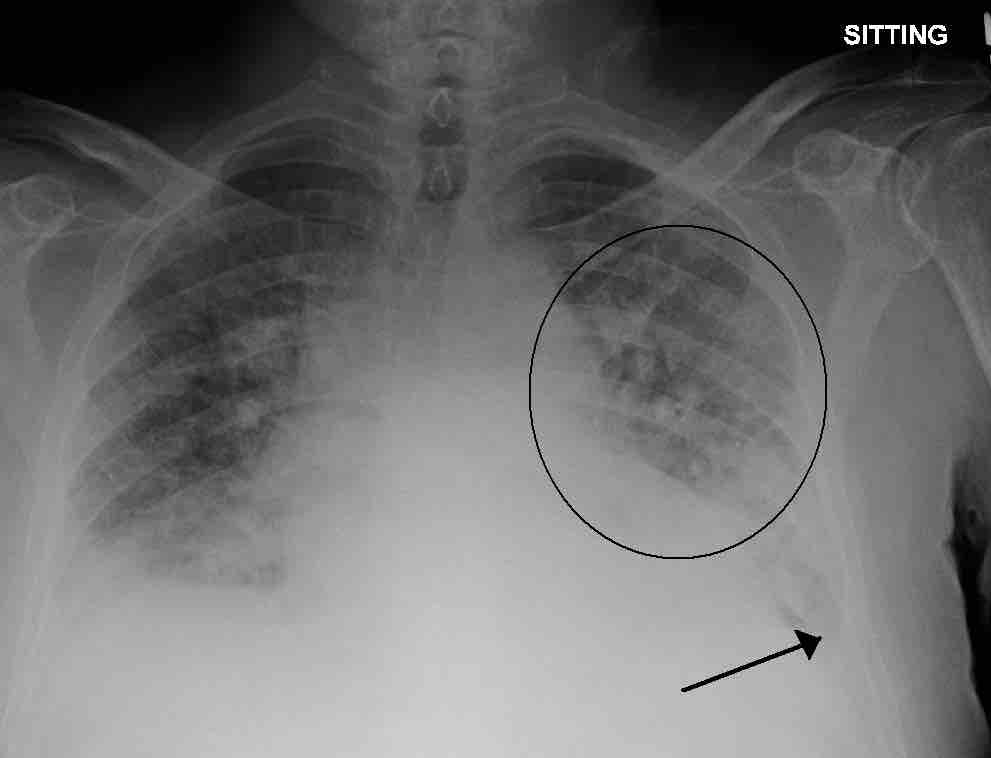

Dead Space: V/Q Mismatch

Pulmonary edema

A physiological shunt can develop if there is infection or edema in the lung which decreases ventilation, but does not affect perfusion; thus, the ventilation/perfusion ratio is affected. Pulmonary edema with small pleural effusions on both sides (as shown) can cause changes in the V/Q ratio.